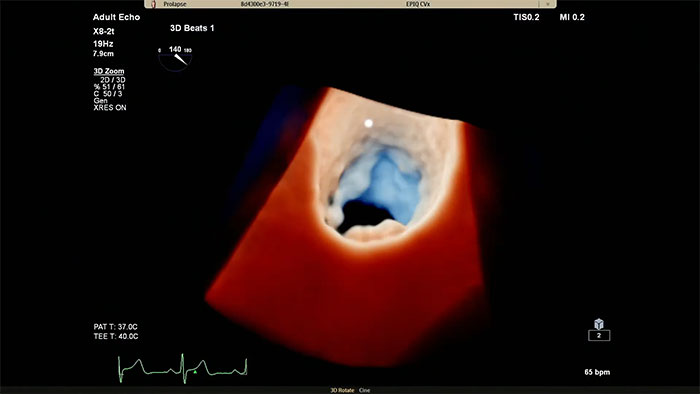

EPIQ CVx – TrueVue Color

Verbesserte Darstellung von Strukturen und Blutfluss mit TrueVue Color

• Besseres Verständnis von strukturellen Veränderungen des Herzens und der davon betroffenen Blutflüsse zur sicheren Durchführung des geeigneten Verfahrens